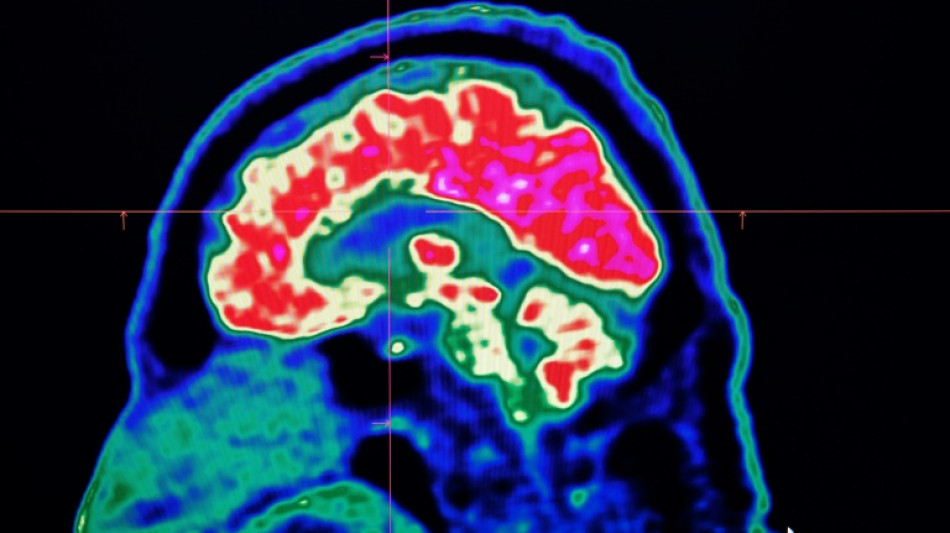

Surging nervous system disorders now top cause of illness: study / Photo: Fred TANNEAU - AFP/File

Conditions affecting the nervous system -- such as strokes, migraines and dementia -- have surged past heart disease to become the leading cause of ill health worldwide, a major new analysis said on Friday.

More than 3.4 billion people -- 43 percent of the global population -- experienced a neurological condition in 2021, far more than had previously been thought, the analysis found.